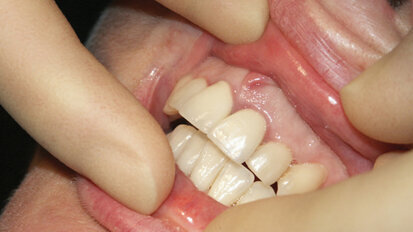

Our 58-year -old patient had a lifetime of periodontal disease and rampant decay. As a young woman, Donna’s dental disease was diagnosed and treatment...

save